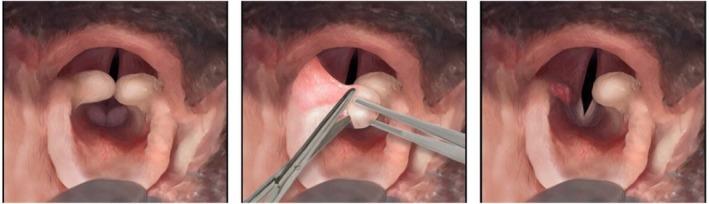

晚期喉塌陷犬行喉楔状切除术的并发症发生率及预后

Complication rate and outcomes of laryngeal cuneiformectomy in dogs with advanced laryngeal collapse.

To describe the complication rate and outcomes of dogs undergoing multilevel airway surgery for brachycephalic airway syndrome (BOAS) with and without the addition of uni- or bilateral cuneiformectomy.

Cuneiformectomy was not associated with a higher incidence risk of complications than multilevel BOAS surgery alone. Significant improvements in respiratory parameters were observed following cuneiformectomy in addition to multilevel airway surgery.

Cuneiformectomy represents a safe and effective adjunctive technique to manage higher grade laryngeal collapse in dogs with BOAS.